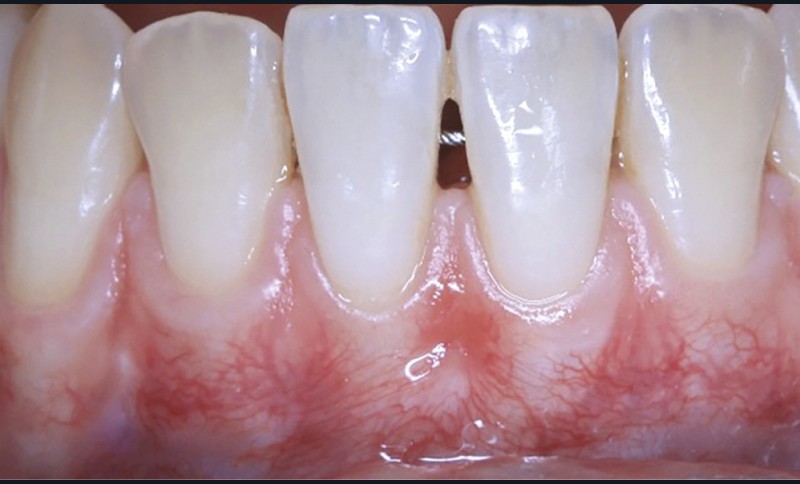

La greffe épithélio-conjonctive (GEC) [7, 8] consiste au remplacement du tissu parodontal existant par un greffon épithélio-conjonctif dont l’indication principale est l’augmentation en hauteur et en épaisseur du tissu kératinisé (fig. 2). Elle peut aussi être utilisée dans le recouvrement radiculaire (avec des résultats en termes de recouvrement inférieurs à ceux des techniques de greffe de conjonctif enfouie), l’aménagement des crêtes édentées, l’aménagement péri-implantaires [9, 10] (fig. 3), ou en association avec un traitement ortho-parodontal [11]. Le principal défaut de cette technique est son aspect inesthétique ; elle sera donc réservée à des zones non visibles comme les incisives mandibulaires ou les zones postérieures.